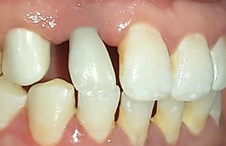

(Figures 13–20) All ceramic crown with a zirconia framework would provide an acceptable aesthetic result. Zirconia framework always requires a try-in step to confirm fit, insertion, retention, and mostly the space left for cosmetic ceramic. After veneering with feldspathic ceramic, and intraoral checking, crowns were glazed, then cemented: A good aesthetic integration was observed: respect of the shape, volume and color of the tooth compared to its counterpart with well distributed diastemas.

Figure 18 Profile views of the definitive crowns.

Figure 19 Final result: discreet smile.

Figure 20 Forced smile.

An asymmetry of the neckline persisted after the prosthesis was placed, but this did not bother the patient, since her smile is purely dental. Functionally, care was taken to integrate the prosthesis into the patient's occlusal context while paying attention to the aesthetic aspect (situation of the free edge of the prosthesis).